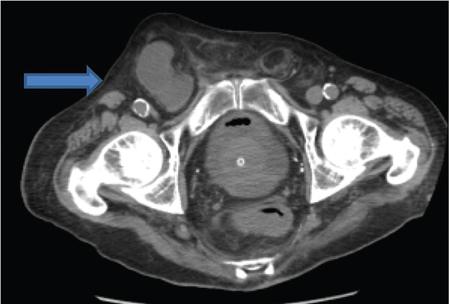

Amandeep Singh The abdominal wall surrounds the anterolateral aspect of the abdominal cavity, where many important organs are located. The abdominal wall is made up of: Superior epigastric artery, inferior epigastric artery, deep circumflex iliac vessels, superficial epigastric vessels and superficial circumflex iliac vessels supply the anterior abdominal wall. Nerves of the anterior abdominal wall include subcostal nerve, iliohypogastric and ilioinguinal nerves. Types of abdominal hernias: The diagnosis of hernia can be made with plain radiographs, barium studies and CT. They consist of a peritoneal sac which protrudes through a weakness/defect in the muscular layers of the abdominal wall (mainly in transversalis fascia below the conjoined tendon). Preperitoneal fat, greater omentum and viscera may protrude into the sac (Fig. 7.15.2). Types: Indirect or direct (depending on their relationship to the inferior epigastric vessels). Indirect hernia: They occur in infants and children. The peritoneal sac passes through the internal ring into inguinal canal, lateral to the inferior epigastric vessels and anterior to the spermatic cord. In women, it goes along the round ligament into the labium. Rarely, the herniated sac instead of leaving the external inguinal ring continues along with the abdominal wall muscles. This is called interparietal hernia (Fig. 7.15.3). Direct hernia: It is always acquired. The herniated sac is medial to the inferior epigastric vessels and does not pass through the inguinal canal. Hence, they do not reach up to scrotum. Femoral hernias are less common than inguinal hernias. They are more common in paediatric age groups and women. The predisposing feature is the empty space between the lacunar ligament medially and the femoral vein laterally. Physical changes of pregnancy dilate this space. The herniated sac is below the inguinal ligament and lateral to the femoral vessels. Strangulation is a common complication. In femoral hernia, the sac lies below and lateral to the pubic tubercle as it emerges from the femoral canal. It can be differentiated from an inguinal hernia which lies above and medial to the pubic tubercle (Fig. 7.15.4). Incisional hernias occur as a result of complication of laparotomy. Risk factors include old age, obesity, postoperative wound infection, chronic pulmonary disease, cirrhosis, malignant tumour, steroids and malnutrition. Most of these hernias develop during the first few months after surgery but may remain silent for up to a period of 5 years. Incisional hernia are more likely to occur as a result of vertical incisions than transverse incisions. They may occur following incisions as small as a puncture site for laparoscopic surgery. A common variation is the parastomal hernia, in which bowel and omental fat protrude through a defect immediately adjacent to an ileostomy or colostomy opening. Bowel loops may be incorporated into the hernia and become incarcerated or strangulated, if the hernia is not treated (Fig. 7.15.5). Richter’s hernia is a rare type of hernia which includes only a part of the bowel wall. Because only a portion of the intestinal wall is included into the hernia, therefore, the lumen remains patent and does not result in obstruction. However, incarceration is not common. Any hernia which contains a Meckel’s diverticulum is known as Littre hernia. They may occur due to the presence of inflammatory adhesions that cause confinement of the Meckel’s diverticulum within the hernia sac. Approximately 50% of Littre hernias develop in the inguinal region, 20% in the femoral, 20% in umbilical and 10% in other sites. Spigelian hernia is a rare acquired ventral hernia that occurs through the linea semilunaris, the line where lateral rectus sheath is formed by fusion of sheaths of lateral abdominal muscles. They are almost always found just above the point where posterior wall of the rectus sheath is pierced by the inferior epigastric vessels. It occurs at midpoint between the umbilicus and symphysis pubis, which is a weak point along the lateral border of the rectus muscle. They are rare but have a high frequency of incarceration and strangulation. It may be mistaken for an abdominal wall lipoma, if it contains only peritoneal fat. CT can be quite beneficial to confirm the diagnosis (Fig. 7.15.6).